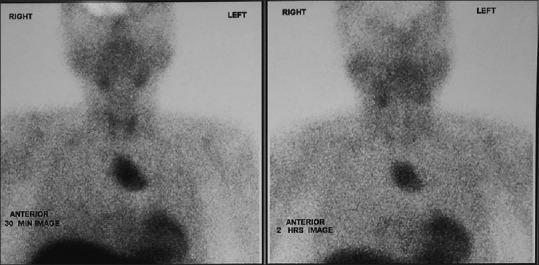

Large Mediastinal Parathyroid Adenoma Presenting with Acute Pancreatitis.

https://cdn.ncbi.nlm.nih.gov/pmc/blobs/bcdd/7539036/d10d33c0a159/IJEM-24-288-g001.jpg